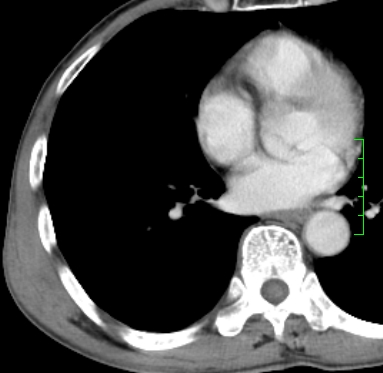

m,73y。膝关节疼痛伴双下肢水肿。入院常规胸片发现结节灶。增强为静脉期。

浅分叶、棘突,考虑右下肺周围型肺癌

肿块周围可见局限性气肿,考虑肺癌可能性大。双肺上叶继发型肺结核。

指套征,强化明显,近侧肺组织局限性肺气肿,考虑支气管类癌,慢支、肺气肿、双上陈旧性tb、冠脉钙化。

鉴别:先天性支气管闭锁,变态反应性支气管肺曲霉菌病,肺癌,支气管囊肿,支扩黏液嵌塞。

1)考虑右肺下叶周围型肺癌。2)右肺上叶及左肺感染性病变(结核可能)。3)肺气肿。4)冠状动脉钙化。